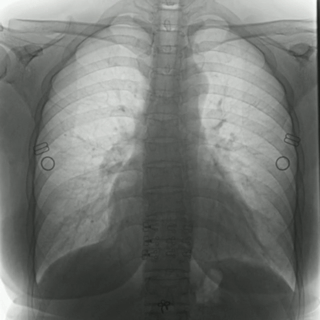

普利德多功能動(dòng)態(tài)DR采用100μm動(dòng)態(tài)平板探測(cè)器,實(shí)現(xiàn)5.0lp/mm超高分辨率成像,大幅提升細(xì)節(jié)檢測(cè)能力;動(dòng)態(tài)檢查幀率高達(dá)30幀/秒,有效避免漏診、誤診;靜態(tài)攝影有效像素高達(dá)1800萬(wàn),較之于傳統(tǒng)900萬(wàn)點(diǎn)片像素,圖像細(xì)節(jié)更加清晰細(xì)膩,有助于醫(yī)生準(zhǔn)確判斷病灶的位置、形態(tài)和大小,為急診救治提供可靠依據(jù)。